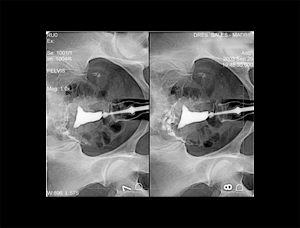

RX Histerosalpingografia

Permite evaluar las características morfológicas de la cavidad uterina y trompas de Falopio. La prueba se realizará en unos días determinados

del ciclo.